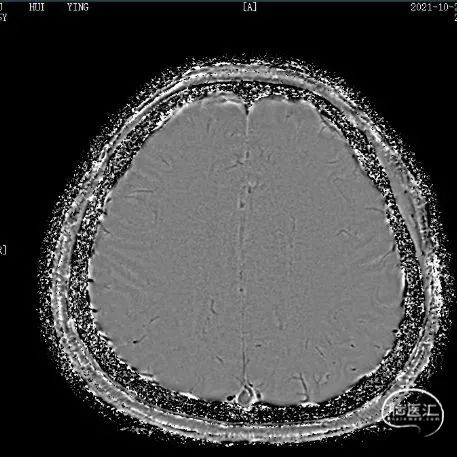

支架植入后造影及3D。

支架植入

支架植入后

术后即刻复查头颅CT未见异常。

术后定期门诊随访,1月以来患者未诉不适,头晕好转,肢体麻木感消失。